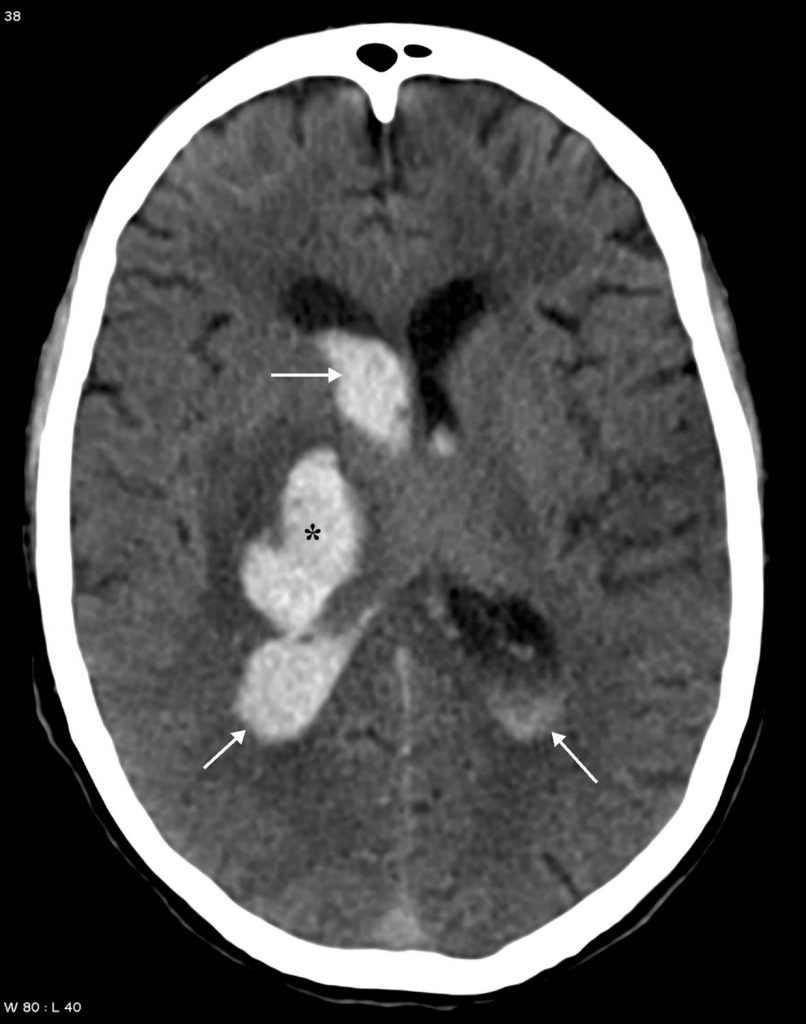

En scanner, le diagnostic est facile : l’hématome apparaît comme une hyperdensité spontanée (sans injection de produit de contraste iodé) intracérébrale responsable d’un effet de masse variable (figures 50.3 et 50.4) pouvant entraîner des signes d’engagement.

Fig. 50.3 Hématome profond chez un patient âgé hypertendu en scanner.

Coupe axiale sans injection de produit de contraste iodé : hyperdensité spontanée (∗) de la région des noyaux gris centraux à droite. Rupture de cet hématome dans le carrefour ventriculaire droit entraînant une hémorragie intraventriculaire avec dilatation ventriculaire (flèches). Pas d’indication à la réalisation d’explorations vasculaires complémentaires.

Source : CERF, CNEBMN, 2022.

Le caractère profond (figure 50.3) ou lobaire (figure 50.4) de l’hématome doit être précisé.

L’hématome peut être associé à :

- une hémorragie intraventriculaire (souvent responsable d’une dilatation ventriculaire) ;